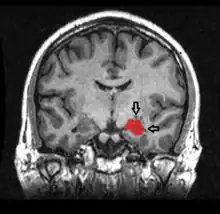

En la enfermedad de Alzheimer el hipocampo es una de las primeras regiones del cerebro en sufrir daño.[1] Los problemas de memoria y desorientación aparecen entre los primeros síntomas. El daño al hipocampo también puede proceder de situaciones de carencia de oxígeno (hipoxia), inflamación del encéfalo (encefalitis) o epilepsia del lóbulo temporal. Las personas que han sufrido un daño extenso en el hipocampo pueden experimentar incapacidad para adquirir o retener nuevos recuerdos (amnesia).

El hipocampo es con frecuencia el foco de los ataques epilépticos: La esclerosis del hipocampo es el tipo más comúnmente visible de daño tisular en la epilepsia del lóbulo temporal.[66] Sin embargo, aún no está claro si la epilepsia está producida por anormalidades en el hipocampo, o bien si éste está dañado por efectos acumulativos de ataques.[67] En condiciones experimentales donde los ataques repetitivos son inducidos artificialmente en animales, el daño en el hipocampo es uno de los resultados frecuentes: Esto puede ser consecuencia de que el hipocampo es una de las partes más eléctricamente excitables del cerebro. También puede estar relacionado con el hecho de que el hipocampo es una de las pocas regiones del cerebro donde la neurogénesis continúa produciéndose a lo largo de la vida.[68]